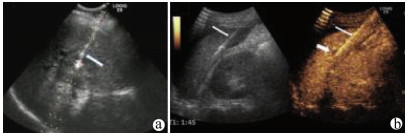

超声造影可指导结直肠癌肝转移患者的治疗策略

隋明巍, 牛俊奇

2021, 37(8): 1928-1928.

摘要(356) HTML (249) PDF (824KB)(41)

摘要: